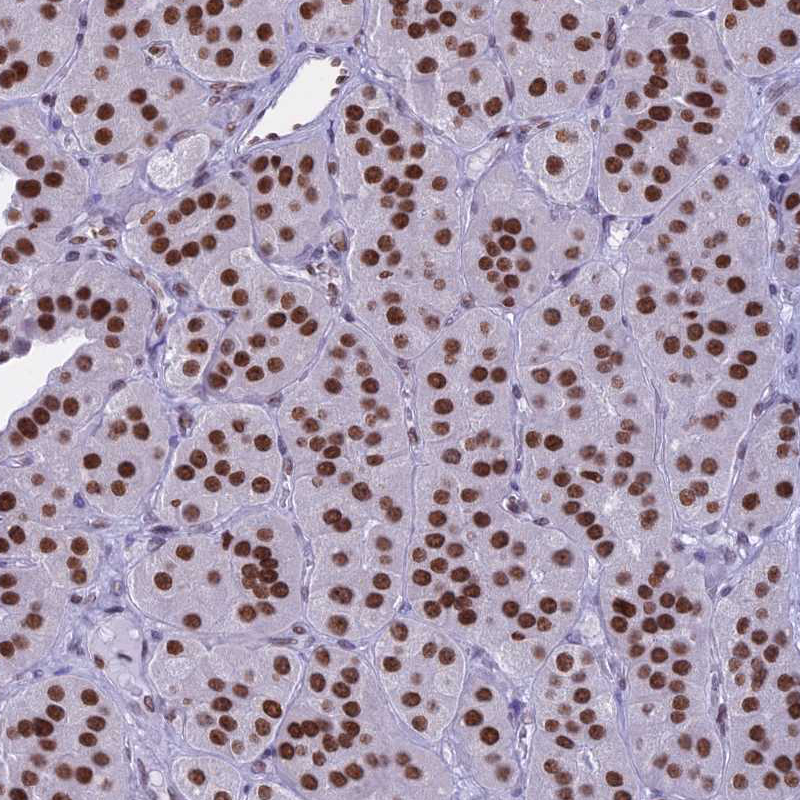

Immunohistochemical staining of human parathyroid gland shows strong nuclear positivity in glandular cells.